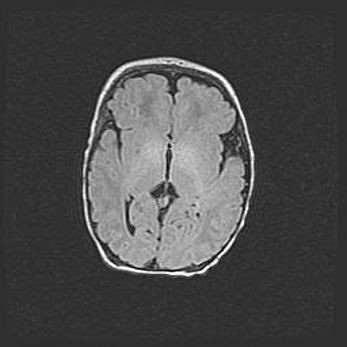

Сообщающаяся гидроцефалия. Кистозная энцефаломаляция головного мозга.

Возраст: 3 месяца 4 дня

Вес: 3100 г

Пол: женский

Окружность головы: 34 см

Срок гестации: 31 неделя

Кистозная энцефаломаляция головного мозга - одна из форм поражения головного мозга в детском возрасте. Характеризуется возникновением множественных и распространённых кист в коре, белом веществе и подкорковых образованиях головного мозга у плодов, новорождённых и детей раннего возраста. Развитие кистозной энцефаломаляции связано с внутриутробной асфиксией и гипотонией, родовой травмой, тромбозом синусов, пороками развития сосудов, инфекциями, сепсисом и другими причинами. Наиболее значимые инфекционные агенты: вирусы простого герпеса, цитомегалии, краснухи, токсоплазмы, энтеробактерии, золотистый стафилококк и другие.